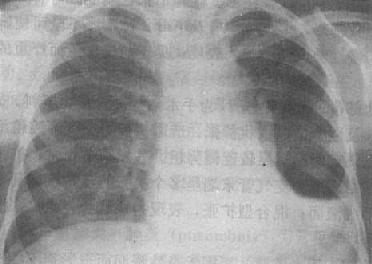

X线表现是病变多发生在两肺中、下野的内、中带。支气管及周围间质的炎变表现为肺纹理增多、增粗和模糊。小叶性渗出与实变则表现为沿肺纺理分布的斑片状模糊致密影,密度不均(图3-1-18)。密集的病变可融合成较大的片状。病变广泛可累及多个肺叶。小儿患者常见肺门影增大、模糊并常伴有局限性肺气肿。

图3-1-18 支气管肺炎

肺门影增大,肺纹理增强、模糊,中、下肺

野可见沿肺纹理分布的斑片状模糊致密影